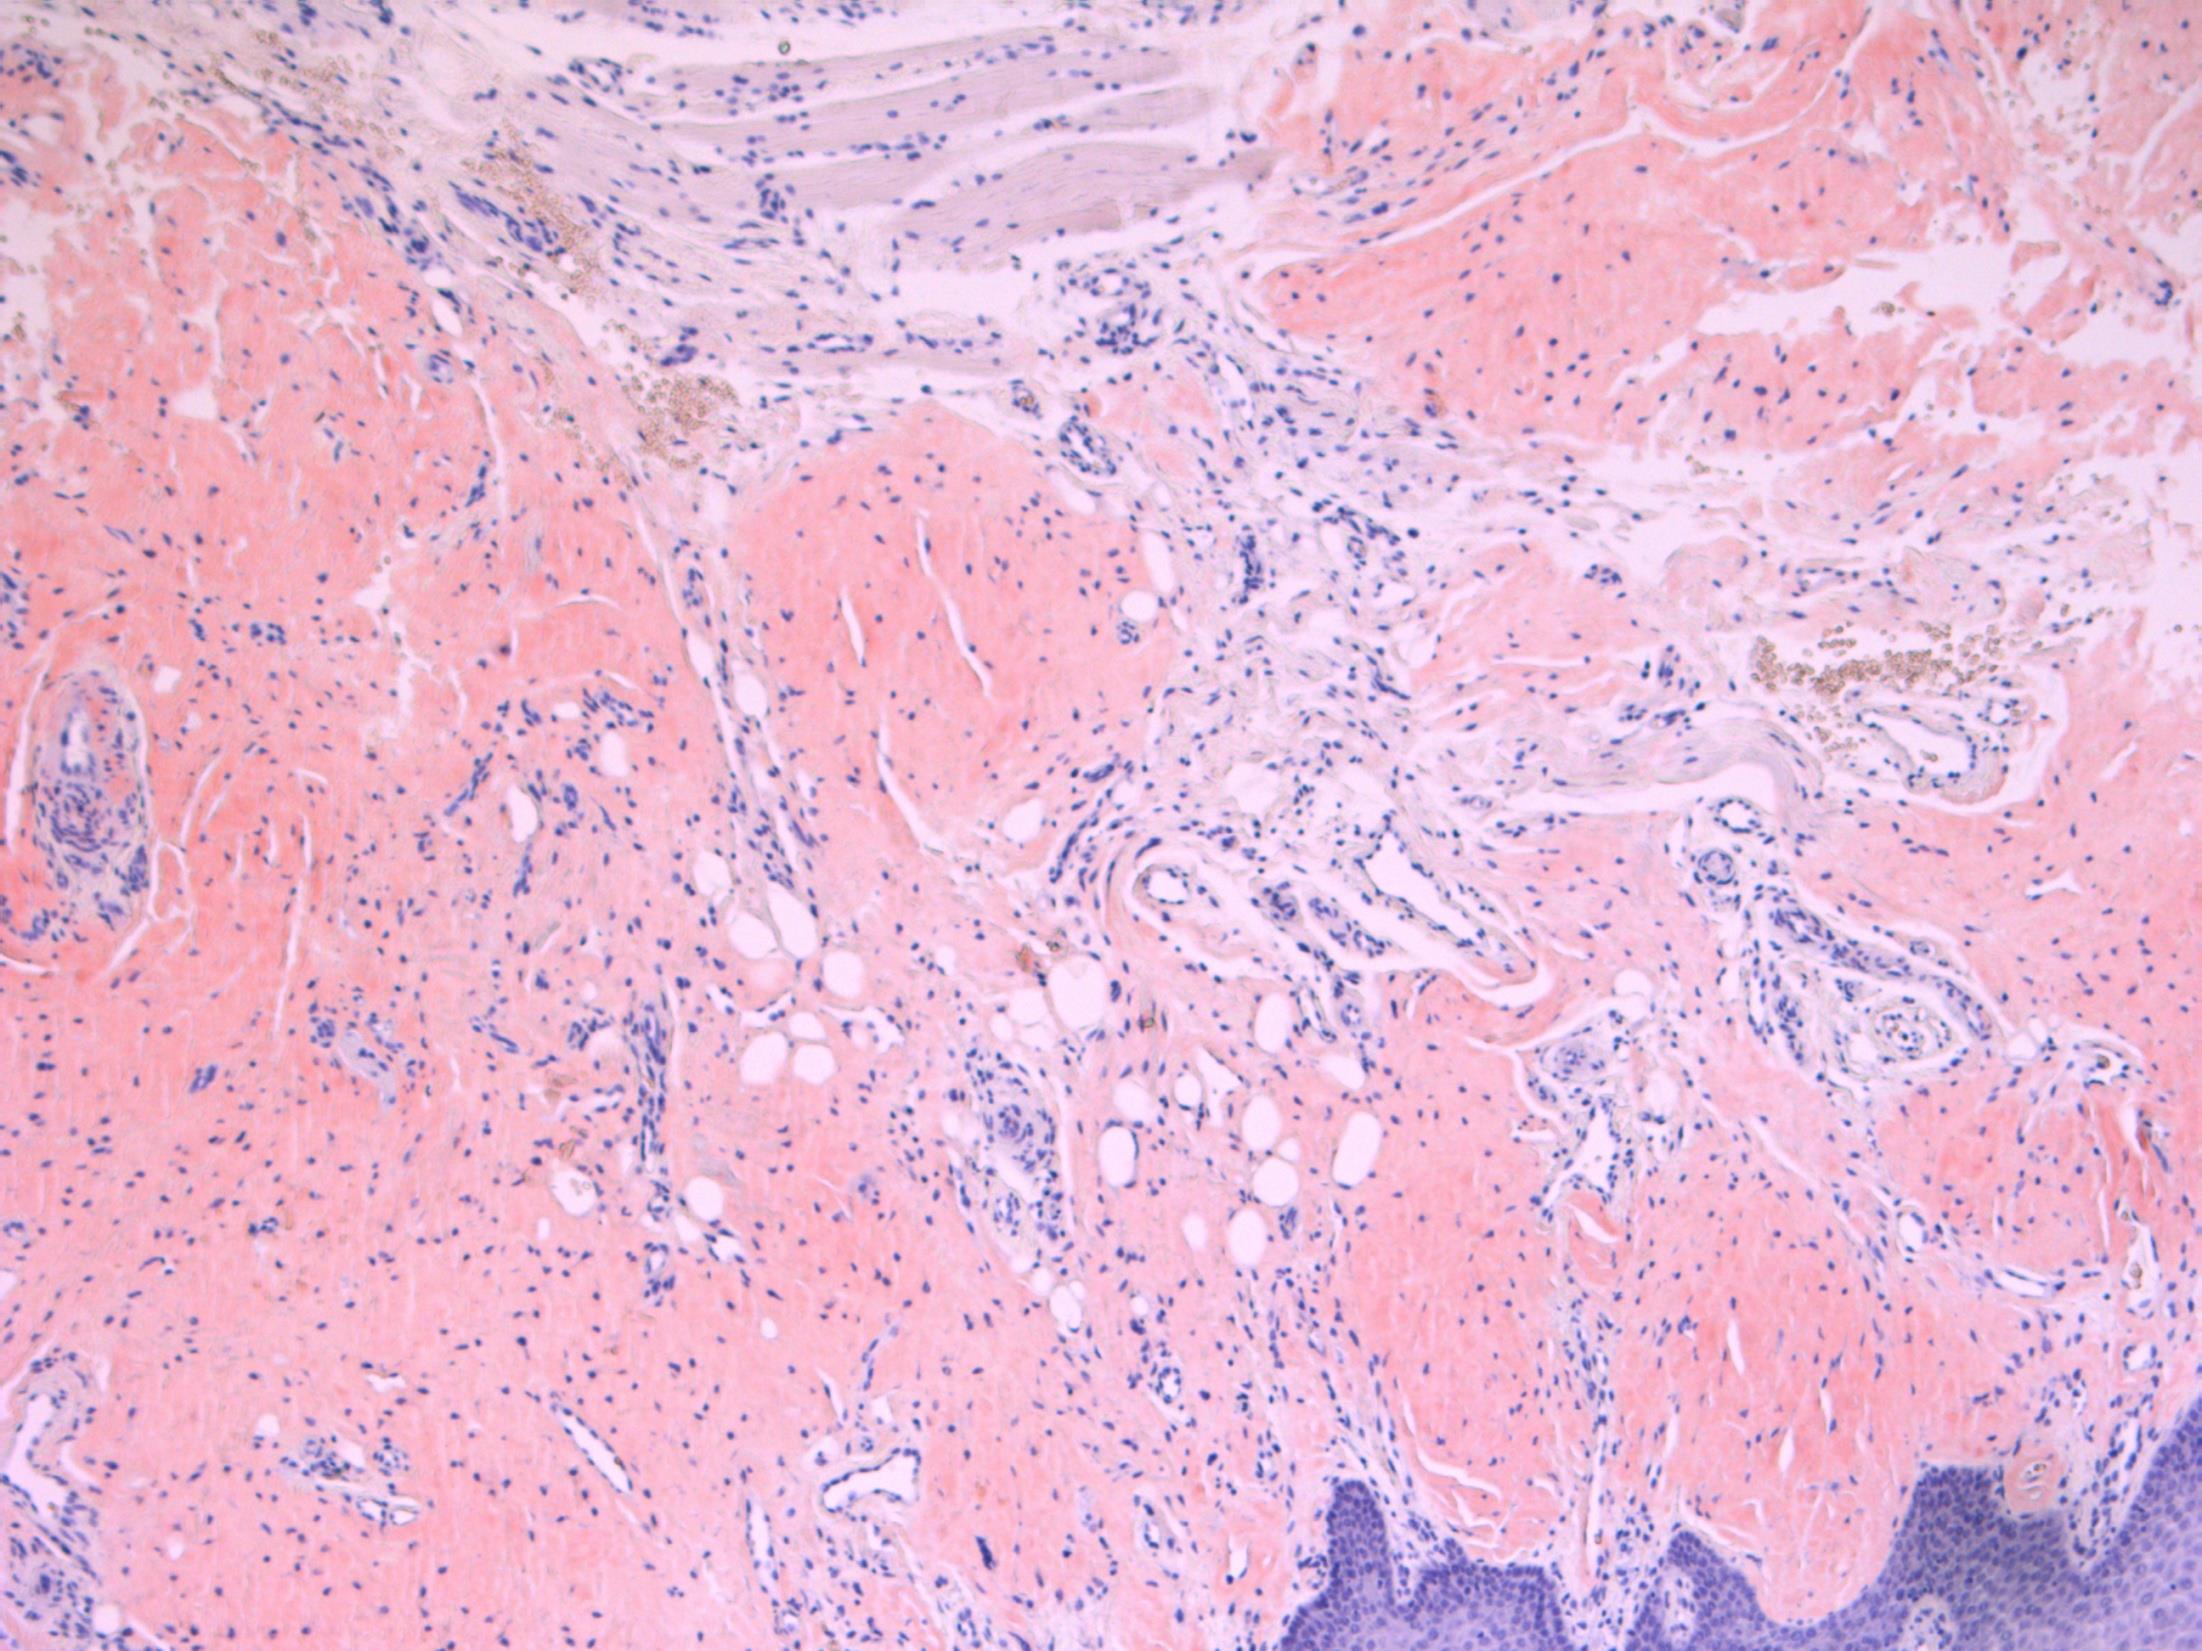

82M. Partial maxillectomy for a 3cm keratotic growth. Two previous biopsies were nonconclusive.

• Maxilla – Verrucous carcinoma

Verrucous carcinoma

Description: Abrupt transition between tumour and epithelium. Plump papillary invaginations of thickened and infolding epithelium, hyperkeratosis. Lack of cytological atypia, suprabasal mitoses. Retraction of normal epithelium at margin. Diagnosis: Verrucous carcinoma Differential Diagnosis:

Conventional SCC – cellular atypia • Squamous papilloma – more exophtyic & branching, less keratin • Reactive inflammatory epithelial hyperplasia – most difficult but rete pegs more slender and anastomosing; no mitoses; macro correlation Plan: Correlate with previous biopsies ( often quite bland so can be inconlusive) Examine further blocks for worse areas and measure margins. Comments: In head and neck – oral cavity and larynx Often large, locally aggressive, pushing margin Better prognosis than SCC

3.5 Clinical features 3.0 Potential differential diagnosis with justification (correlate history too) 2.5 Description with diagnosis 2.0 Differential diagnosis with mention of verrucous carcinoma 1.5 Uncertain, but some mention of ‘atypia’ 1.0 Benign diagnosis Case 19